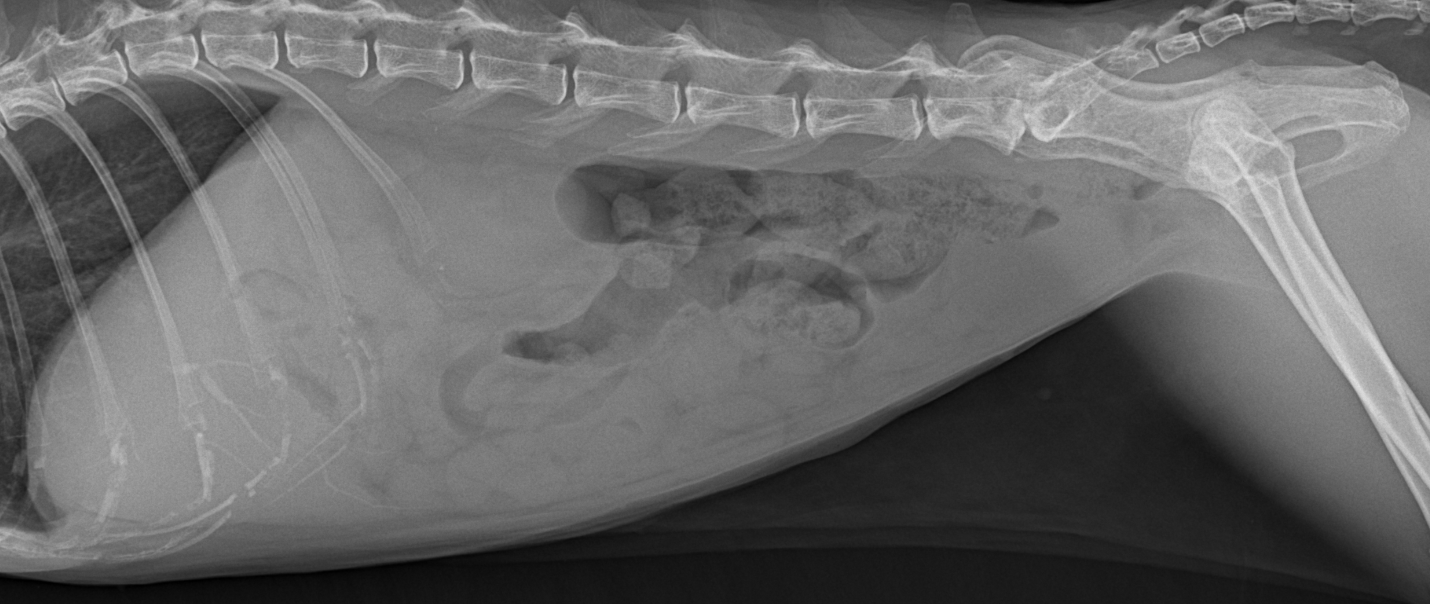

feline intrahepatic bile calculi : radiography

ultrasonography